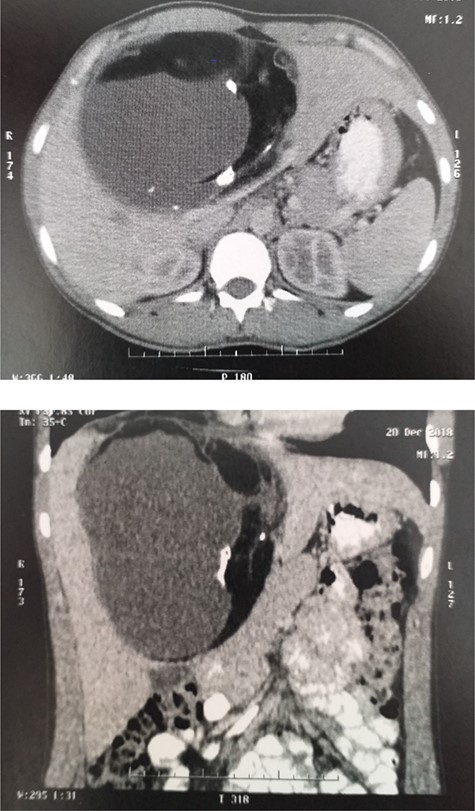

Enhanced CT: ill-defined contrast-enhancing, multilobulated cystic lesion involving segments II, III, VI and VIII.

This is a case of a 27-year-old female who presented with 3 months of loss of appetite associated with mild abdominal distension and a sense of fullness in the right upper quadrant. She had no significant past medical history, with a cigarette smoking habit of consuming one pack per year. On physical examination, no icterus was noted. Mild distention in the right superior quadrant of the abdomen was recognized, a tender and smooth-surfaced mass was identified by liver palpation. Routine clinical investigation revealed a carcinoembryonic antigen of 6.5. All other haematological and biochemical parameters were within the reference range. An abdominal contrast-enhanced computed tomography (CT) showed an ill-defined contrast-enhancing, multilobulated cystic lesion involving segments II, III, VI, VIII measuring 19 × 15 × 10 cm, containing adipose tissue with calcifications and multiple septations (Fig. 1). These findings were suggestive of teratoma. Beta human chorionic gonadotropin and Echinococcus serology were negative. Intraoperatively, a well-defined cyst was confirmed occupying segments IV, V, VIII and partially segments II and III; a mesohepatectomy and cholecystectomy were performed (Fig. 2) with two 15-minute pedicular clampages (Pringle manoeuvre). The right and left hepatic veins were exposed. Due to compression and distortion of the structures, inadvertent opening of the anterior sectorial biliary branch occurred. As a small amount of parenchyma was still draining through this duct, a reconstruction via a Roux-en-Y Hepatico-Yeyunostomy was performed. The patient had an uneventful postoperative evolution, dispatched on day eight. Histopathology reported a surgical specimen with a weight of 1837 g with the dimensions 21 × 18 × 12 cm. The outer surface was smooth and yellowish-grey in colour. The cystic wall had a pattern of irregular thickness, with a maximum thickness of 2 cm with calcified multilobulated areas, containing yellowish sebum paste and hair, the diagnosis was mature cystic teratoma (MCT) (Fig. 3). In subsequent follow-up, patient reintegrated actively in her socio-laboral environment.